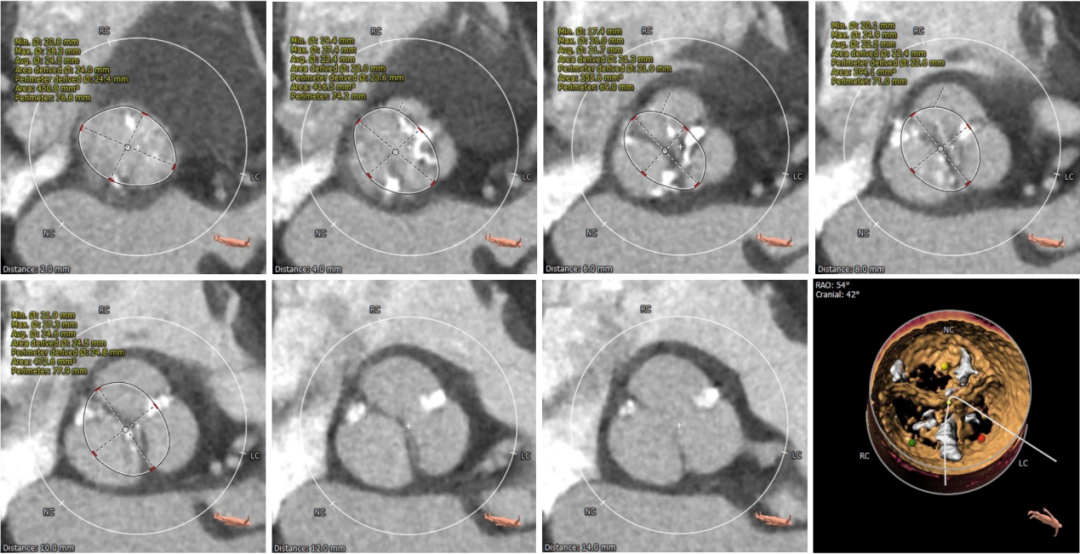

• 预装AV26瓣膜,释放角度推荐RAO 22° CAU 38°(左右重合)左右,释放较高位(瓣环下2mm左右)。释放后调整至左前斜头位进一步确定人工瓣膜形态。手术结束后造影评估入路血管情况,避免遗漏血管并发症情况。

超声检测存在瓣中漏,瓣膜形态不佳,于是用22mm球囊后扩,最终造影显示瓣膜位置合适,冠脉灌注良好,左右钙化嵴处微量瓣周漏。

球囊后扩

术后根部造影

手术即刻超声评估,主动脉瓣工作良好,轻微瓣周漏。